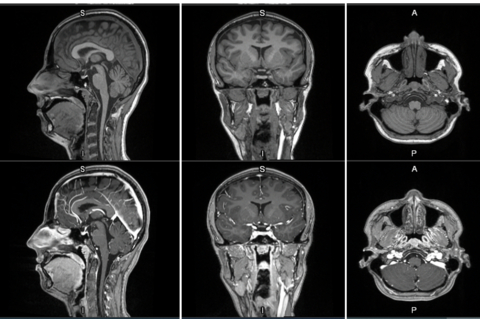

MRI contrast agents enhance the visualization of abnormal structures or lesions during imaging procedures and help clinicians better distinguish between healthy and diseased tissue. Mangaciclanol is intended for general-purpose MR imaging and demonstrates comparable relaxivity (the ability to enhance signal intensity) to market-leading gadolinium-based agent, gadobutrol, with early clinical images suggesting similar diagnostic capability. Unlike gadolinium, which is a rare-earth metal, manganese is present in our food, and is an endogenous element, naturally occurring and autoregulated in the body. The macrocyclic ‘cage-like’ structure of mangaciclanol lessens the possibility of retention.

First-in-human contrast enhanced MRI images with GE HealthCare's mangaciclanol